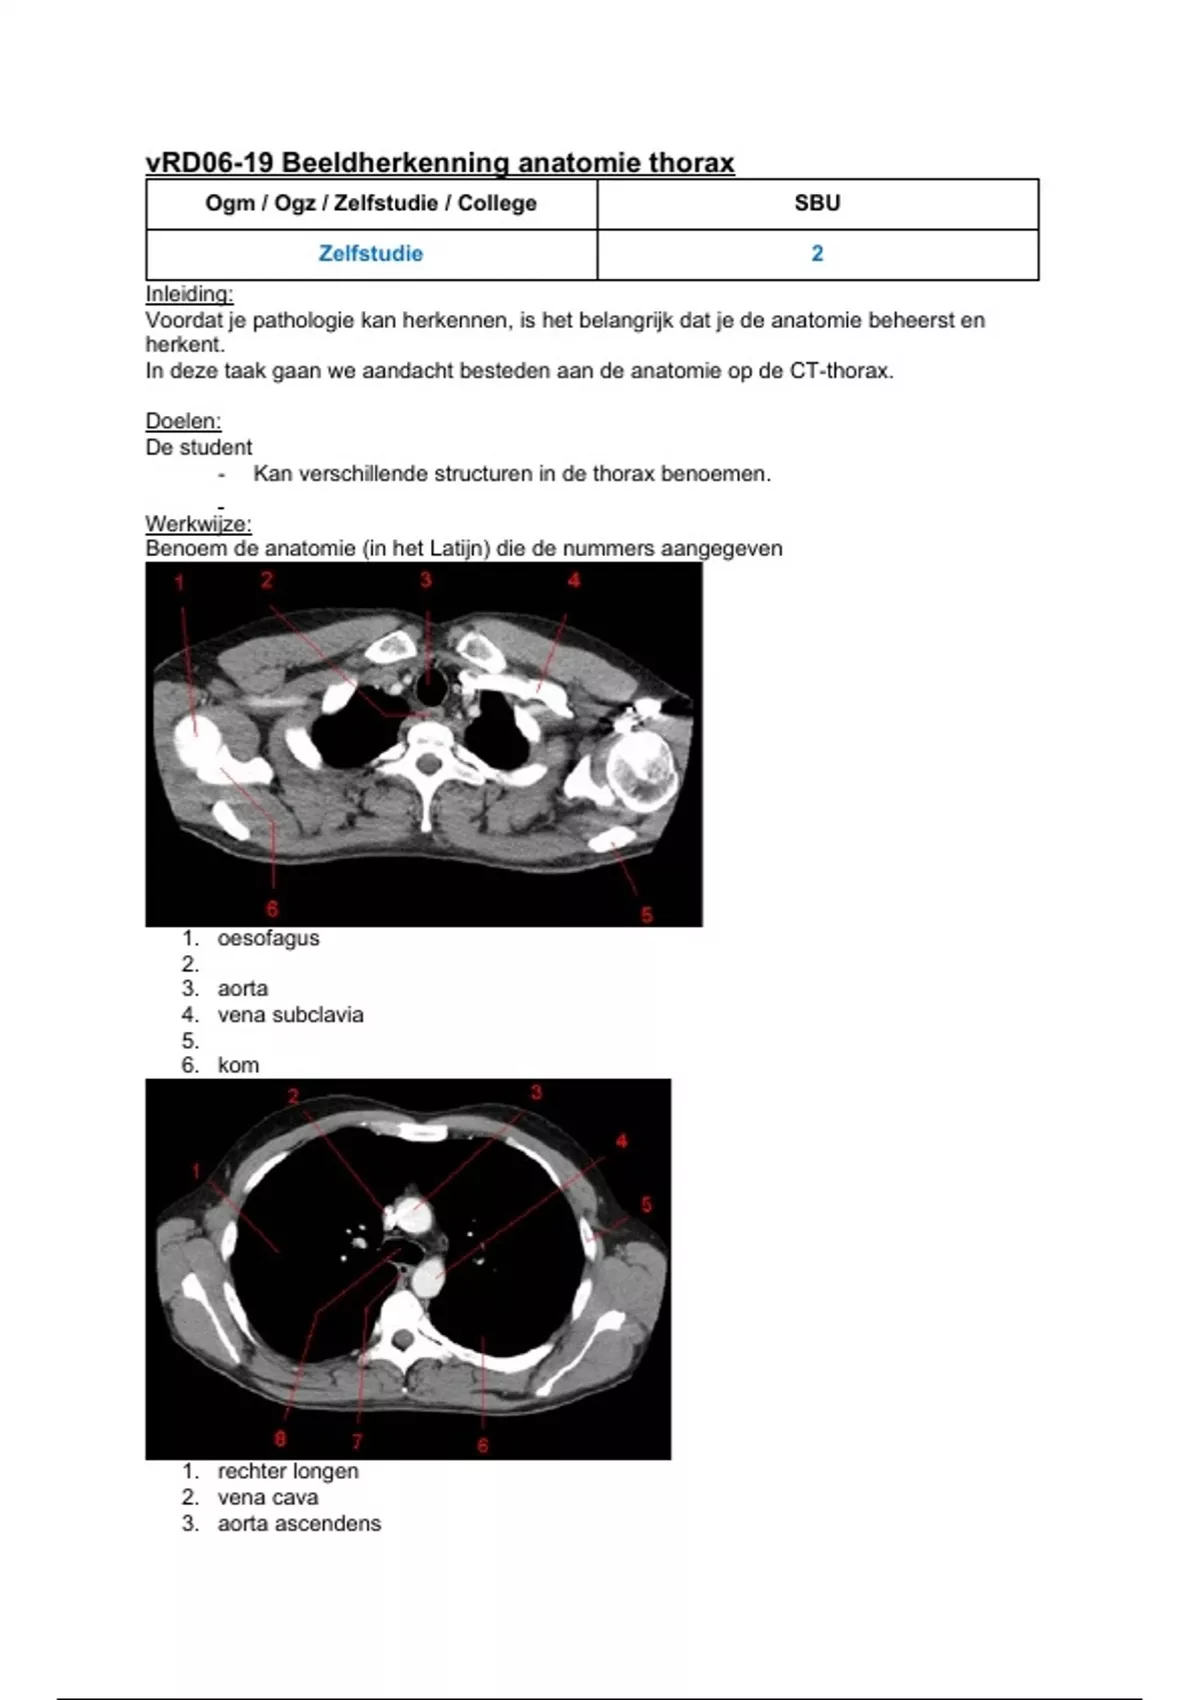

vRD06-19 Beeldherkenning anatomie thorax

Ogm / Ogz / Zelfstudie / College SBU

Zelfstudie 2

Inleiding:

Voordat je pathologie kan herkennen, is het belangrijk dat je de anatomie beheerst en

herkent.

In deze taak gaan we aandacht besteden aan de anatomie op de CT-thorax.

Doelen:

De student

- Kan verschillende structuren in de thorax benoemen.

Werkwijze:

Benoem de anatomie (in het Latijn) die de nummers aangegeven

1. oesofagus

2.

3. aorta

4. vena subclavia

5.

6. kom

1. rechter longen

2. vena cava

3. aorta ascendens